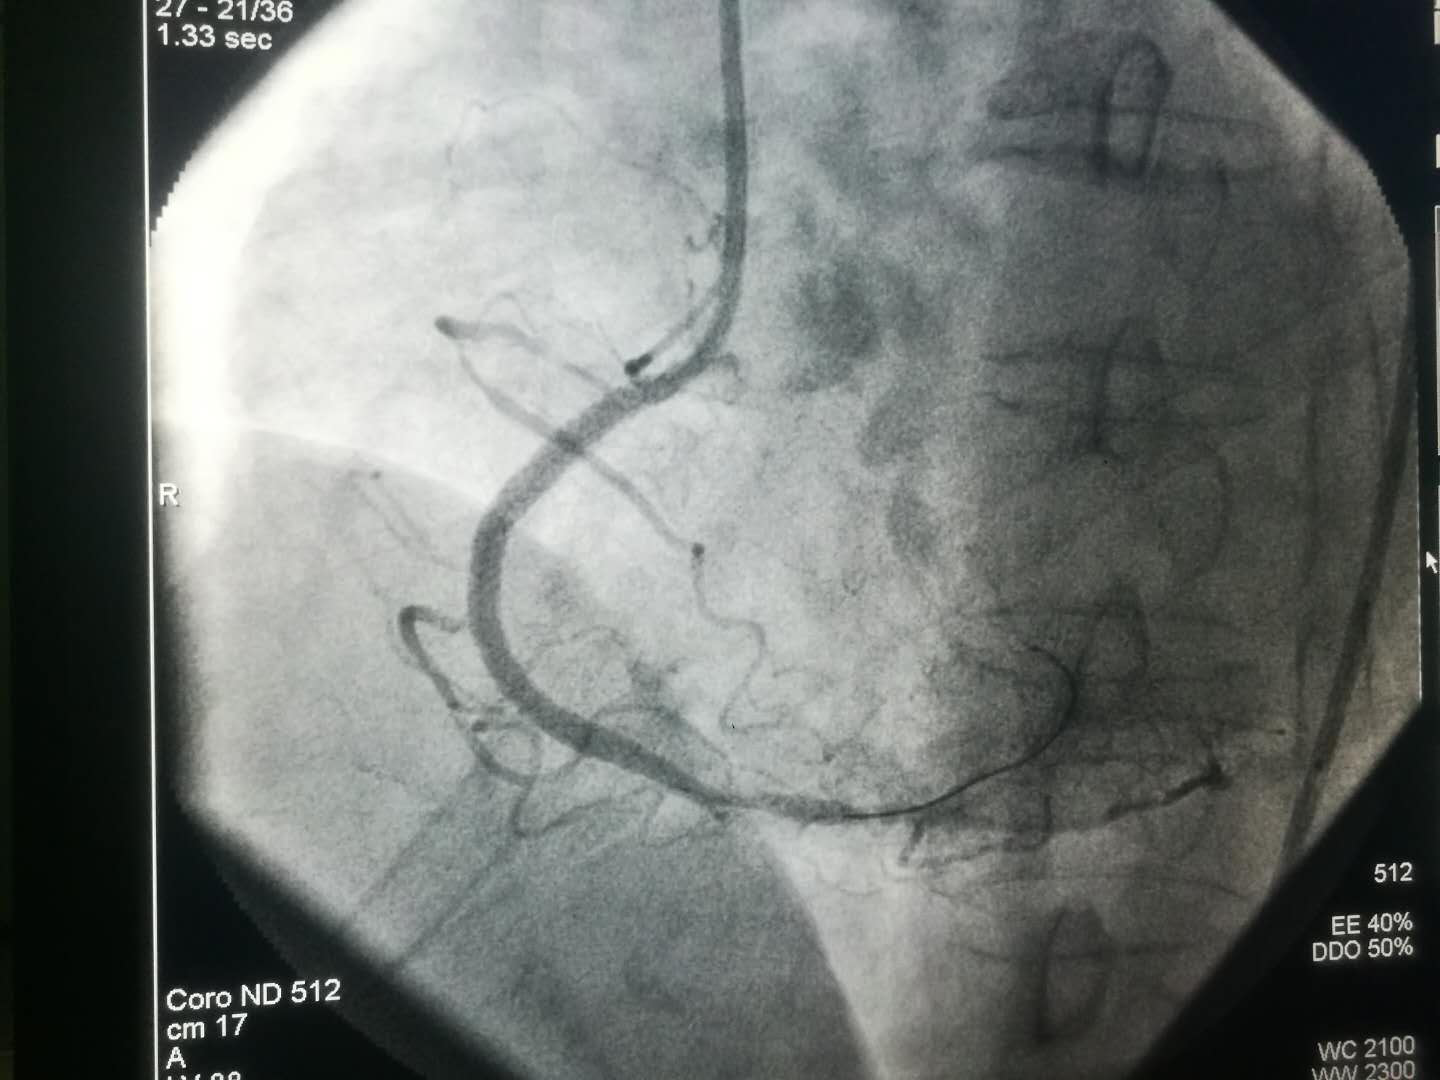

2019新年伊始,文理病区开展了首例冠状动脉造影术及冠状动脉支架植入术。

1月8日上午患者术后在李同华主任的协助下完成文理病区首例冠状动脉造影术加冠状动脉支架植入术。术后患者转入心内四病区监护48小时,1月9日患者平安转回我科继续治疗。整个转诊过程无缝衔接,配合顺畅心血管病医院的各位主任护士长们纷纷表示,只要文理病区需要,术后患者可以转往心血管医院任何一个病区监护。距离无法阻隔我们发展的脚步,无法阻隔我们团结一致为患者服务的信心。